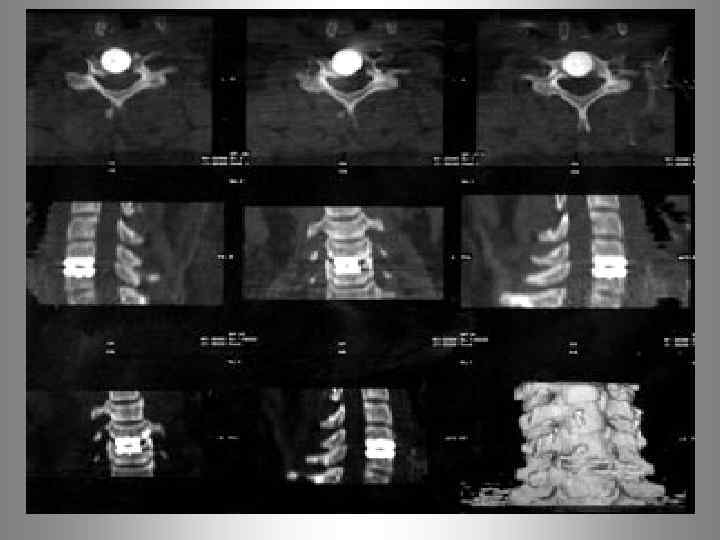

MRT - позвоночника. Спондилит L 2 - L 3 позвонков.